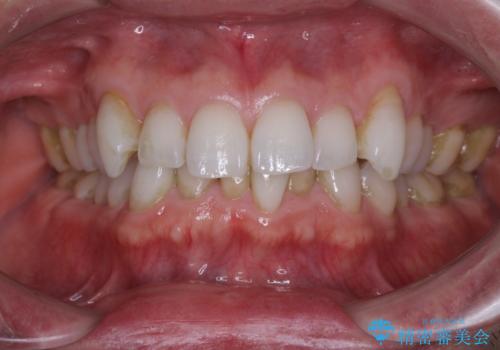

前歯のがたつきをなおしたい マウスピース矯正

担当医 大元洋佑

![[ マウスピース矯正 ] 前歯の角度・がたつきを治したい。の症例 治療前](https://seimitsushinbi.jp/wp/wp-content/uploads/2024/02/IMG_7820-500x350.jpg?v=1707810350)

![[ マウスピース矯正 ] 前歯の角度・がたつきを治したい。の症例 治療後](https://seimitsushinbi.jp/wp/wp-content/uploads/2024/02/8334681fa61954fc45ff8cef14f33166-500x350.jpg?v=1707810480)